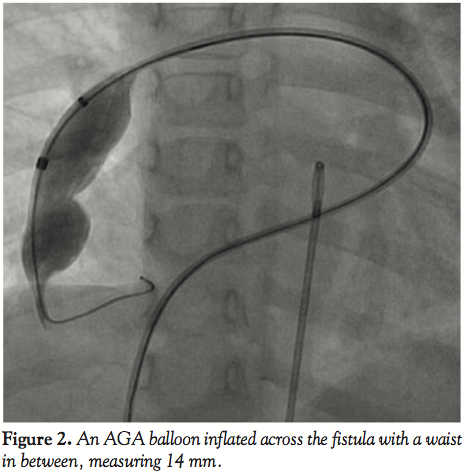

with a large aneurysmal sac of the left atrium (Figure 1, Video 1). The fistula was crossed with the multipurpose catheter and 0.035-inch Terumo wire and this was exchanged with 0.035-inch Amplatz extrastiff exchange length wire that was parked with a good loop in the left atrium. We introduced a 24 mm AGA sizing balloon to occlude the vessel, rule out additional fistula, and to measure the narrowest portion of the feeder as it entered the left atrium (Figure 2, Video 2). The communication was

single and the narrow segment measured 14 mm with the proximal portion measuring 26 mm. Considering the morphology of the fistula, we decided to close the defect antegradely. As the fistula was large and roomy we decided to close the feeding vessel with an atrial septal occluder. The left atrial disc would easily be accommodated in the aneurysmal sac and the right atrial disc was expected to configure into the shape of the feeding artery without protruding into the lumen of RPA. The constricted segment was well away from the branches of the RPA as well as the opening of the pulmonary veins into the left atrium. The balloon was removed and an 8 Fr long Cook sheath was introduced antegradely over the Amplatz wire through RPA, across the fistula into the LA. As the constricted segment measured 14 mm, we deployed a 16 mm Cardiofix atrial septal occluder (Starway Medical Corporation) across the narrow portion of the feeding vessel. While the left atrial disc assumed the expected shape, the right atrial disc was rounded due to comparatively less space in the feeding artery. We did RPA injections in multiple views to be sure that there was no obstruction to RPA flow as well as that there is no residual flow across the fistula (Figure 3, Video 3). After checking the stability of the device, it was released (Figure 4, Video 4). The patient’s saturation improved to 100% and there was no residual fistula on follow-up. He was put on oral aspirin for 6 months and is doing well on follow-up without any complications.